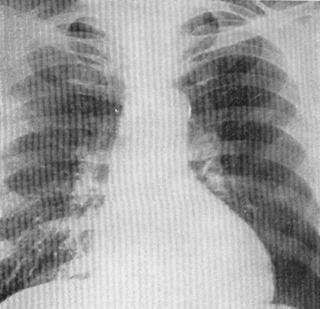

Рис. 101. Рентгенограмма больного со стенозом аортального клапана.

Этот шум проводится на сосуды шеи, в яремную и надключичные ямки. Для выраженного аортального стеноза характерно снижение пульсового давления. Это обусловлено тем, что систолическое давление понижено, а диастолическое давление остается нормальным. При этом пульс малый со склонностью к брадикардии. При рентенологическом обследовании имеет место, так называемая аортальная конфигурация сердца. Для нее характерно резкое увеличение левого желудочка по левому контуру с подчеркнутой талией сердца. Отмечается постстенотическое расширение восходящей аорты, четко выявляемое в левой косой проекции (рис. 101). Во время электрокардиографического исследования определяется гипертрофия левого желудочка (левограмма, увеличение зубца Р в 5-м и 6-м грудных отведениях, смещение вниз интервала ST в левых отведениях). Регистрация отрицательных зубцов Т в 1-ом и 2-ом стандартных отведениях является показателем относительной коронарной недостаточности. На фонокардиограмме фиксируется ромбовидный или веретенообразный систолический шум над аортой во втором межреберье справа. При ЭхоКГ выявляется степень сужения аортального отверстия, состояние створок, объемы полостей сердца, а также выраженная гипертрофия левого желудочка. У пациентов в возрасте старше 40 лет, страдающих аортальным стенозом, показано проведение коронарографии для исключения ИБС.